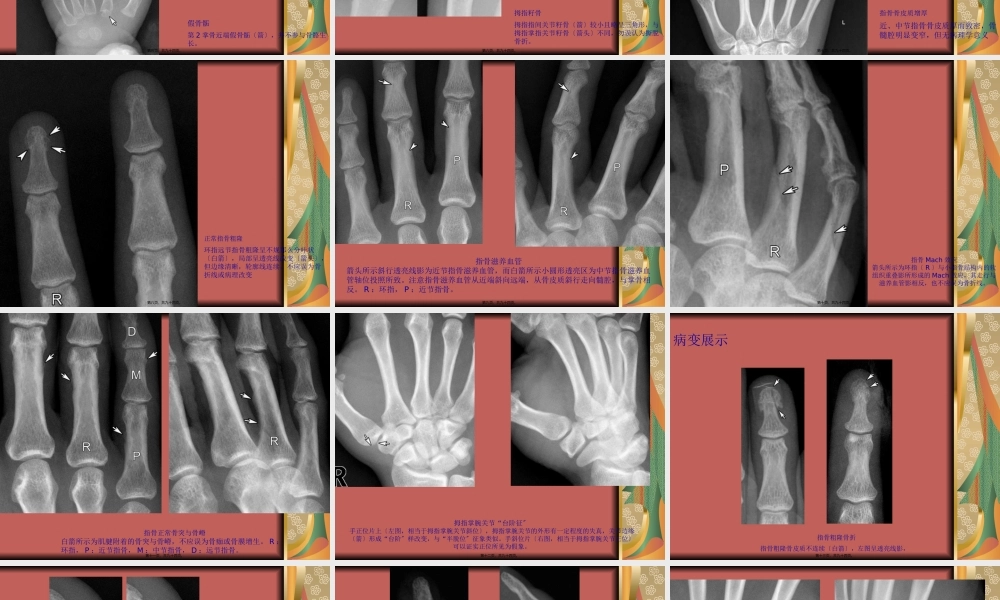

四肢关节正常变异、常见病变及创伤的影像表现第一页,共九十四页。一、手第二页,共九十四页。成人手正斜位1.远节指骨2.中节指骨3.近节指骨4.第4掌骨5.拇指远节6.拇指近节7.远节指骨粗隆8.指骨头〔指骨滑车〕9.指骨干10.指骨底11.掌骨头12.掌骨干13.掌骨底14.远侧指间关节15.近侧指间关节16.掌指关节17.腕掌关节18.大多角骨19.小多角骨20.头状骨21.钩骨22.籽骨第三页,共九十四页。男性生长期手正位第四页,共九十四页。正常变异及易混淆结构假骨骺第2掌骨近端假骨骺〔箭〕,并不参与骨骼生长。第五页,共九十四页。拇指籽骨拇指指间关节籽骨〔箭〕较小且略呈三角形,与拇指掌指关节籽骨〔箭头〕不同,勿误认为撕脱骨折。第六页,共九十四页。指骨骨皮质增厚近、中节指骨骨皮质厚而致密,骨髓腔明显变窄,但无病理学意义第七页,共九十四页。正常指骨粗隆环指远节指骨粗隆呈不规那么分叶状〔白箭〕,局部呈透亮线改变〔箭头〕,但边缘清晰,轮廓线连续,不应误为骨折线或病理改变第八页,共九十四页。指骨滋养血管箭头所示斜行透亮线影为近节指骨滋养血管,而白箭所示小圆形透亮区为中节指骨滋养血管轴位投照所致。注意指骨滋养血管从近端斜向远端,从骨皮质斜行走向髓腔,与掌骨相反。R:环指,P:近节指骨。第九页,共九十四页。指骨Mach效应箭头所示为环指〔R〕与小指骨结构内的软组织重叠影所形成的Mach效应,其走行与滋养血管影相反,也不应误为骨折线。第十页,共九十四页。指骨正常骨突与骨嵴白箭所示为肌腱附着的骨突与骨嵴,不应误为骨痂或骨膜增生。R:环指,P:近节指骨,M:中节指骨,D:远节指骨。第十一页,共九十四页。拇指掌腕关节“台阶征〞手正位片上〔左图,相当于拇指掌腕关节斜位〕,拇指掌腕关节的外形有一定程度的失真,关节边缘〔箭〕形成“台阶〞样改变,与“半脱位〞征象类似。手斜位片〔右图,相当于拇指掌腕关节正位〕可以证实正位所见为假象。第十二页,共九十四页。病变展示指骨粗隆骨折指骨粗隆骨皮质不连续〔白箭〕,左图呈透亮线影,第十三页,共九十四页。拇指近节裂纹骨折伴籽骨撕脱注意裂纹骨折〔白箭〕与滋养血管影〔箭头〕的鉴别。拇指指间关节间隙籽骨〔黑箭〕不在正常位置第十四页,共九十四页。远节指骨骨折附着于末节指骨的伸肌腱断裂,伴或不伴有撕脱骨折。本例小指远节指骨基底部缺损〔箭〕与小骨片〔箭头〕根本吻合,可以与籽骨鉴别。另外,此小骨片形态密度与籽骨亦不相同。第十五页,共九十四页。...